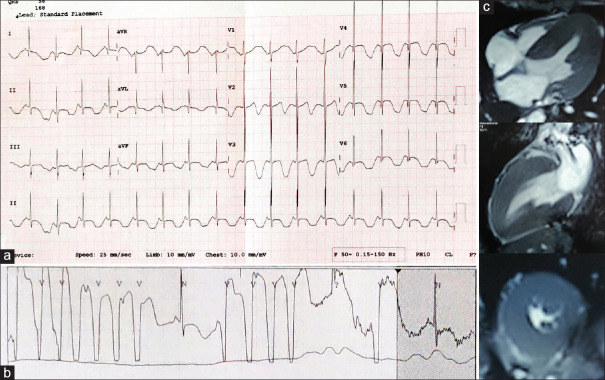

An 11-year-old boy presented with recurrent exertional syncope for 1 month. The baseline electrocardiogram (ECG) suggested a diagnosis of long QT syndrome with macroscopic T-wave alternans. Volatility of blood pressure and left ventricular hypertrophy triggered further investigations, revealing pheochromocytoma as the primary cause. The child underwent laparoscopic resection of the tumor with subsequent resolution of ECG changes and symptoms. The genetic testing was negative for known mutations implicated with prolonged QT interval.

一个11岁的男孩表现为反复的劳力性晕厥1个月。基线心电图(ECG)提示长QT综合征的诊断与宏观t波交替。血压波动和左心室肥厚引发了进一步的调查,发现嗜铬细胞瘤是主要原因。患儿行腹腔镜肿瘤切除术,随后心电图改变和症状得到缓解。基因检测与QT间期延长有关的已知突变呈阴性。